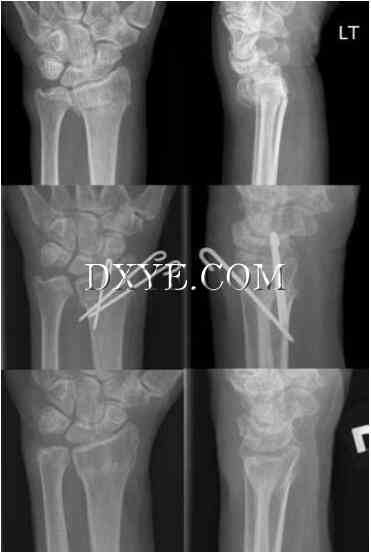

桡骨远端骨折畸形愈合是常见的,可能是关节外,关节内,或两者。只有对症畸形需要手术干预。老年低需求患者无痛且功能良好,尽管有明显的影像学缺陷,但无需干预。然而,与更高的功能要求,在年轻的成年人的畸形愈合可导致疼痛、丧失运动和畸形。如果桡骨背倾斜大于25°到30°,桡骨和尺骨之间相差6毫米,则需要外科介入治疗。这可能包括矫正桡骨远端截骨(延长)或缩短尺骨截骨。桡骨远端截骨手术的目的是恢复掌倾角、桡骨高度,和桡骨倾斜和提高运动的屈伸弧(图76.19)。尺骨截骨用于尺侧撞击和尺侧腕痛。Darrach程序(的尺骨小头切除术)与尺在老年患者选择的程序方面的手腕疼痛。有限的或全腕关节融合或Sauve -Kapandji手术可在症状患者桡腕及桡尺关节炎,分别表示。

19.jpg

图 76.19.  修复桡骨远端骨折的桡骨远端截骨术。 A.术前X线片显示桡骨高度和倾向的损失和显著的背部倾斜与尺侧阳性方差。 B.术后早期X线片显示半径矫正截骨术后影像学参数的矫正。